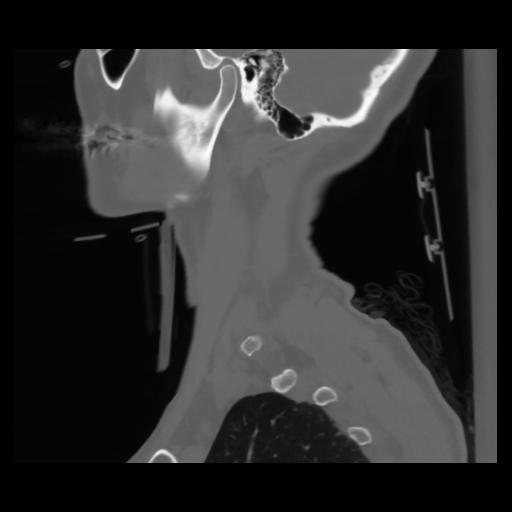

14 P.BLANDAS,,Sagittal,2.000,P.BLANDAS,Sagittal,